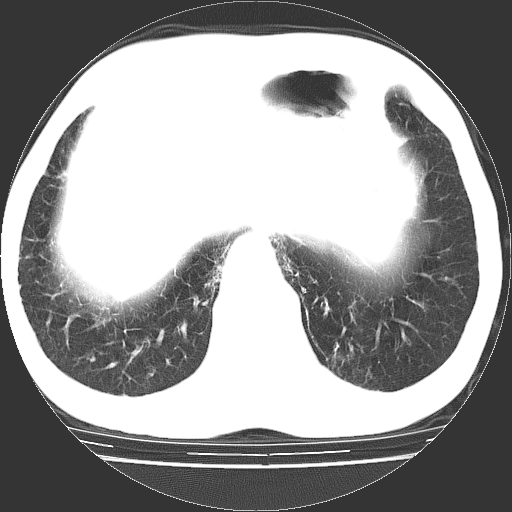

以下是引用hhcckk在2009-1-1 15:38:00的发言:[br]左下肺少许絮状模糊影--考虑感染[br]两肺散在小点状密度增高影--结合病史考虑矽肺?[br]气管壁钙化--可能由于老年退变性引起的